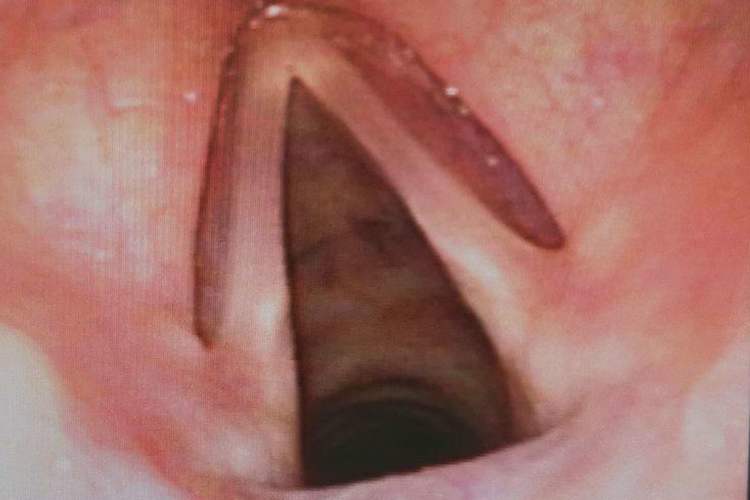

儿童喉咙正常由环状软骨、会厌软骨等软骨构成,喉咙内壁可见有淡红色黏膜,喉镜下可见圆环状软骨,无红肿等异常表现。

儿童喉咙正常由环状软骨、会厌软骨、甲状软骨、杓状软骨、小角软骨和楔状软骨构成,外表附着有韧带及肌肉,喉黏膜内衬喉腔。正常时喉咙无炎症反应,黏膜呈淡红色,表面滑润,喉镜下可见有淡红色圆环状软骨,儿童吞咽时无疼痛、吞咽困难、干痒等表现。